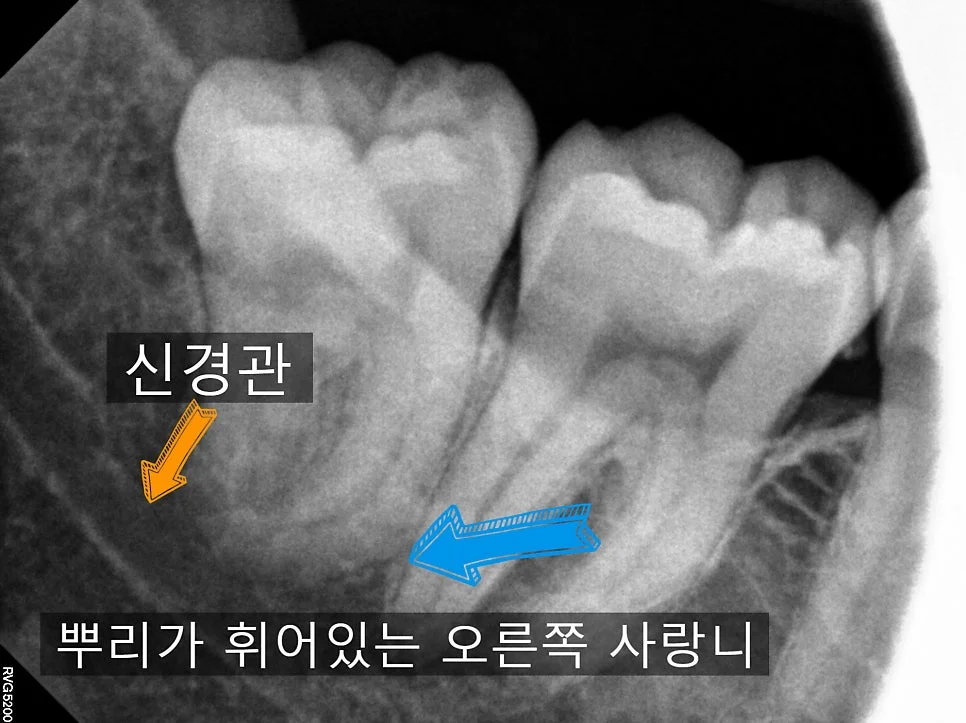

오른쪽 사랑니 확대 — 오렌지색 화살표(신경관), 파란색 화살표(휜 뿌리)

오른쪽 사랑니는 겉으로 보기엔 단순해 보였지만, 뿌리 끝이 심하게 휘어 있고 신경관과 맞닿아 있었습니다.

이런 경우에는 치아가 한 번에 안 나오니까, 머리와 뿌리를 나눠서 발치해야 합니다. 난도가 높은 편이라 보통 15~20분 정도 걸리는데, 단계별로 차근차근 발치를 해주면 됩니다.

물론 듣기만 해도 “어려운 발치”처럼 느껴지실 텐데, 걱정하지 않으셔도 됩니다. 이런 케이스를 깔끔하게 뽑아낼 수 있다면, 사랑니 발치 경험이 정말 풍부하다고 볼 수 있게죠.^^